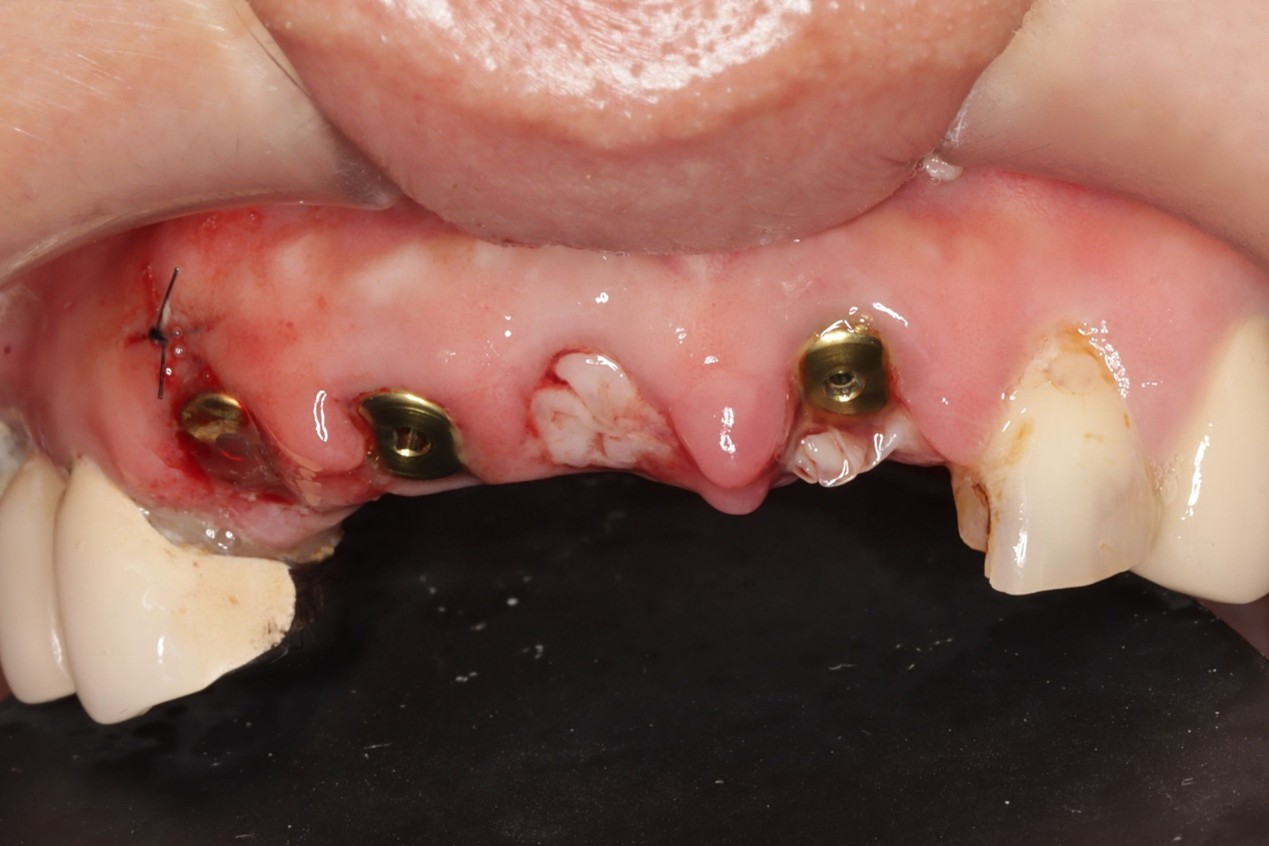

同步反應口腔位置,讓醫師能即時避開血管、神經、縮小創口,達到「真・微創植牙」,加速術後癒合,幫助患者迅速找回笑容自信,讓植牙也能成為無上體驗。

- 創口小癒合快,達到「真・微創植牙」

安適準導航植牙系統可以於植體製作前(術前)做第一次植牙流程規劃,判讀病患牙齒間狀況,並做出最合適的植牙療程建議。搭載高達12顆鏡頭,於手術間幾乎零死角定位植牙位置,配合AI高速運算,讓植體精準的植入齒骨,創造幾乎與原生牙齒無二的舒適感。